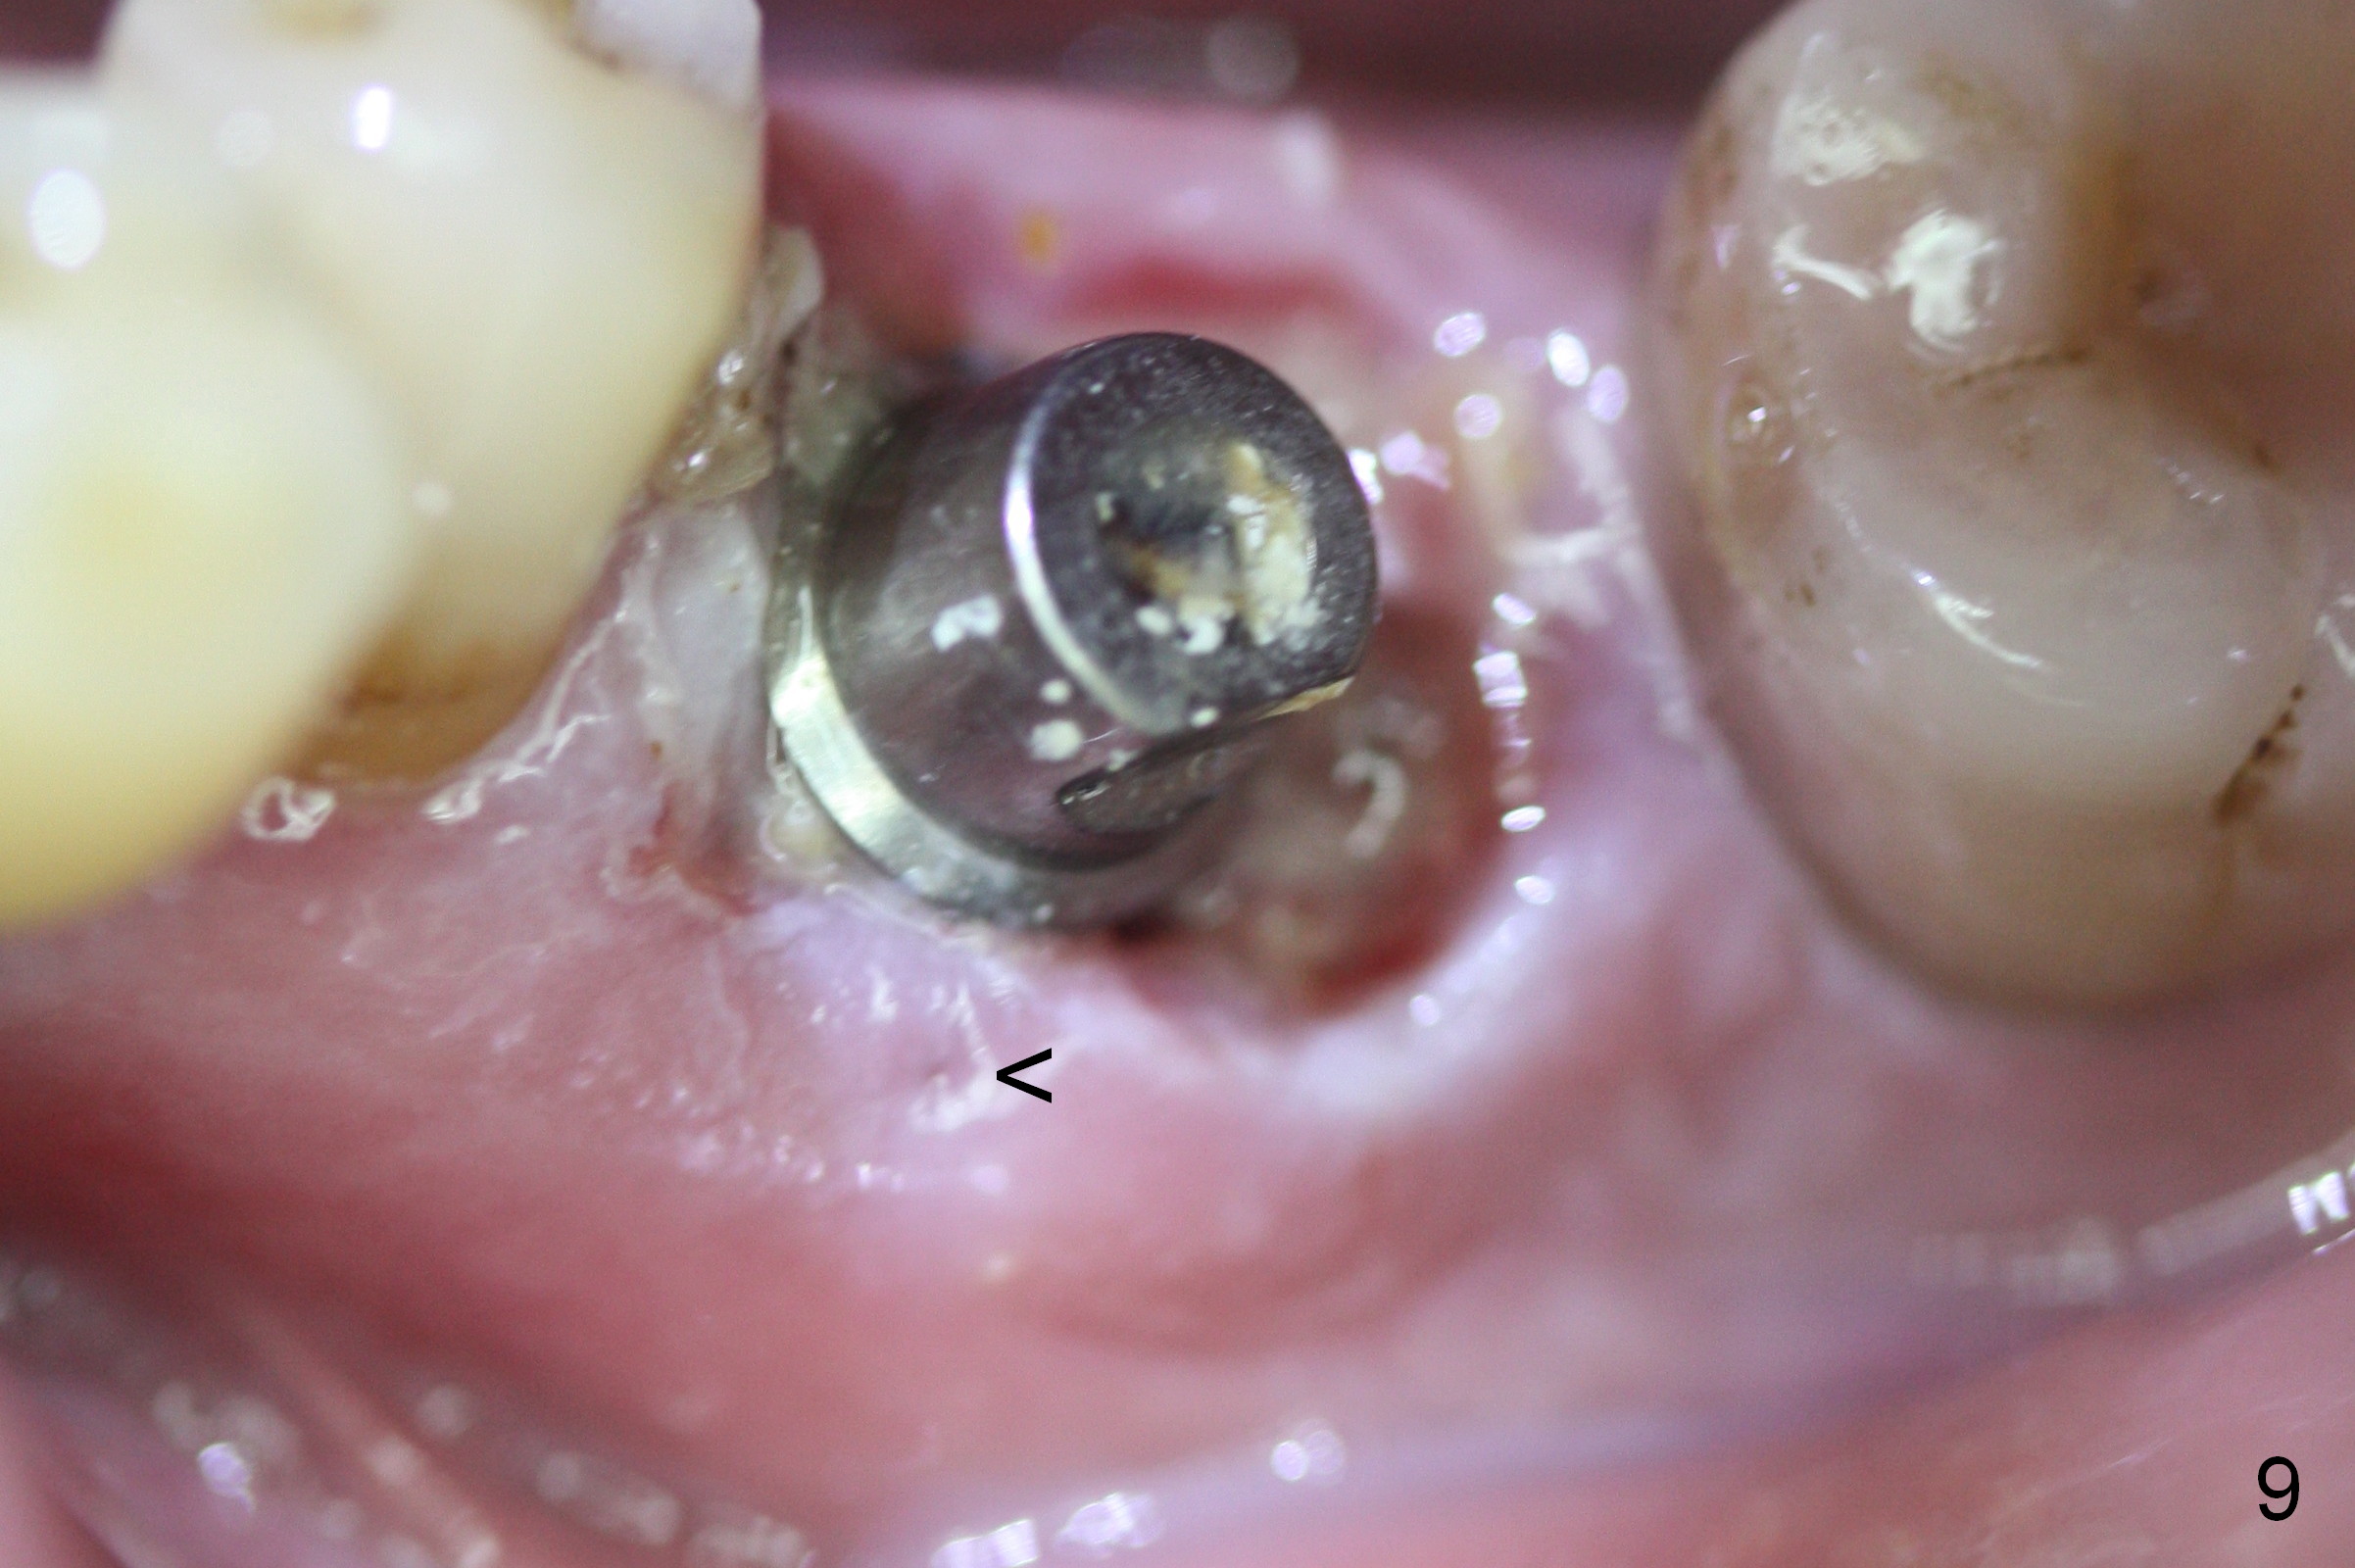

The patient remains asymptomatic 6 days postop (Fig.8,9). The fistula is resolving (Fig.9 <). The provisional is removed for reline.